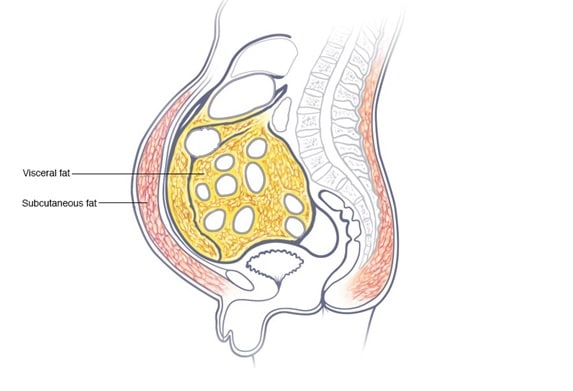

Belly fat is a more dangerous fat. The trouble with belly fat is that it’s not limited to the extra layer of padding located just below the skin (subcutaneous fat). It also includes visceral fat — which lies deep inside your abdomen, surrounding your internal organs. Regardless of your overall weight, having a large amount of belly fat increases your risk of: